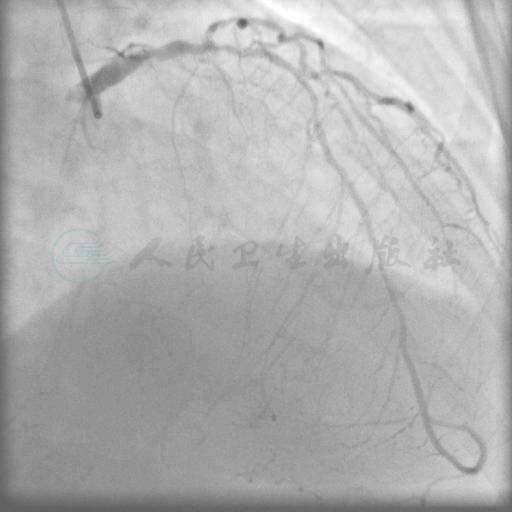

冠状动脉右优势型,左主干体部80%狭窄,左回旋支纤细开口70%狭窄,前降支全程管壁不规则,近中段弥漫狭窄,局部狭窄70%~80%,右冠状动脉近端CTO病变,远端由来自同侧及左冠状动脉侧支逆供显影(以同侧为主)(图1、图2)。Syntax评分:38.5分。

图1 左主干病变,前降支病变弥漫性病变

图2 右冠状动脉近段闭塞病变